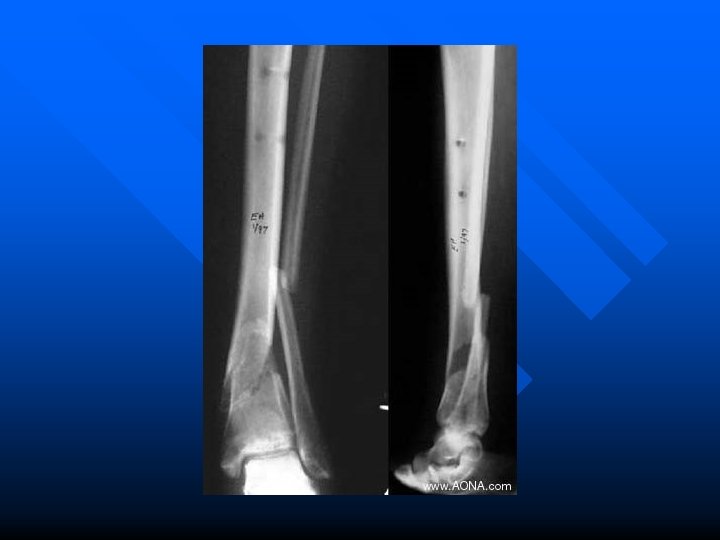

Leg Fractures n. Direct blows or indirect trauma

Stress Fractures An incomplete break in a bone occurring after prolonged repetitive exercise

Stress Fractures (con’t) n Signs and Symptoms -